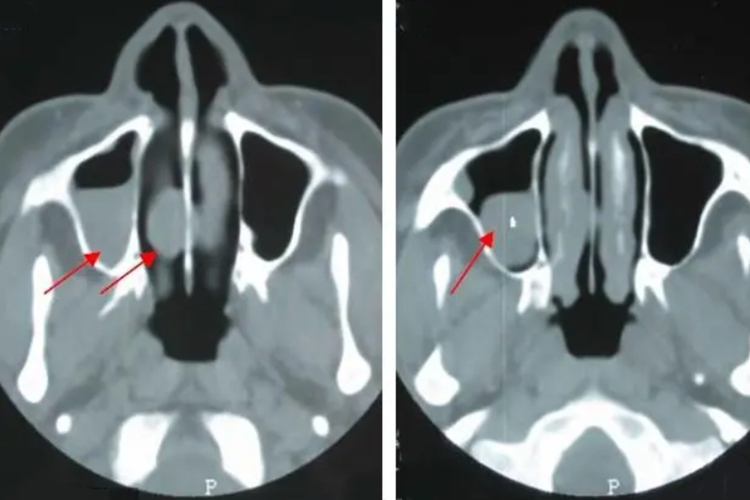

鼻窦囊肿呈膨胀性生长,压迫窦壁及其邻近结构,可致眶顶(额窦)、眶内(筛窦)、面颊与上腭(上颌窦)等处的局部膨隆,触之表面光滑,按压如乒乓球状。鼻腔外侧壁可因囊肿压迫而向内侧移位,引起鼻塞、流涕、嗅觉减退等表现。鼻窦X线片或CT扫描可显示窦内囊肿影,局部穿刺可抽出囊液。